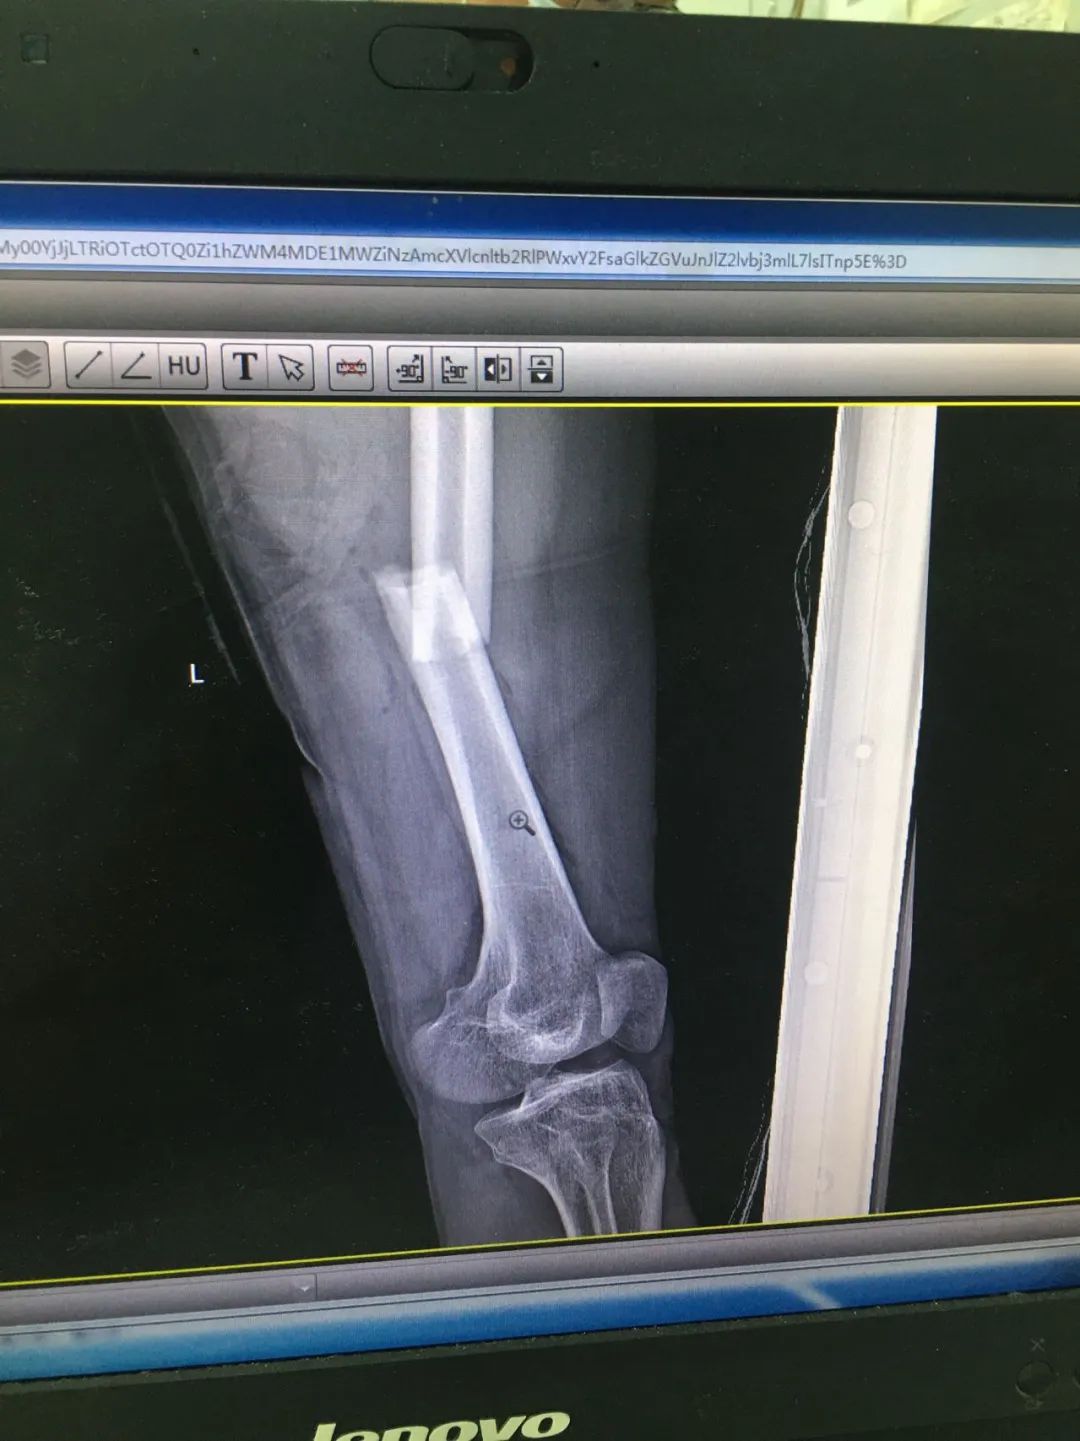

入院時(shí),劉先生已失血性休克。急診科為劉先生安排X線及CT攝片檢查,顯示左股骨干、左腓骨上端骨折,左脛骨遠(yuǎn)端粉碎性骨折,頭皮及全身多處皮膚軟組織挫裂傷,隨后收治于骨科。

骨科徐自勝醫(yī)生為劉先生仔細(xì)查體后發(fā)現(xiàn),其頭頂部偏左位置有一長(zhǎng)約3cm的傷口,深達(dá)顱骨,周?chē)醒E;左股骨中段位置畸形、腫脹,肉眼可見(jiàn)一道長(zhǎng)約5cm的傷口,有血液流出,局部壓痛陽(yáng)性;左小腿遠(yuǎn)端腫脹、畸形,也有一道2cm的傷口,左下肢活動(dòng)嚴(yán)重受限。

第1次手術(shù)10天后,骨科為劉先生安排了第2次手術(shù),歷經(jīng)3個(gè)小時(shí),成功完成左股骨干骨折及左脛骨遠(yuǎn)端骨折閉合復(fù)位內(nèi)固定術(shù),植入兩根30cm×10mm、34cm×10mm髓內(nèi)釘。

術(shù)后一周,患者手術(shù)切口愈合良好,左下肢皮膚感覺(jué)及肌力正常,左足末梢循環(huán)恢復(fù),復(fù)查X片顯示骨折復(fù)位標(biāo)準(zhǔn),內(nèi)固定物位置良好。